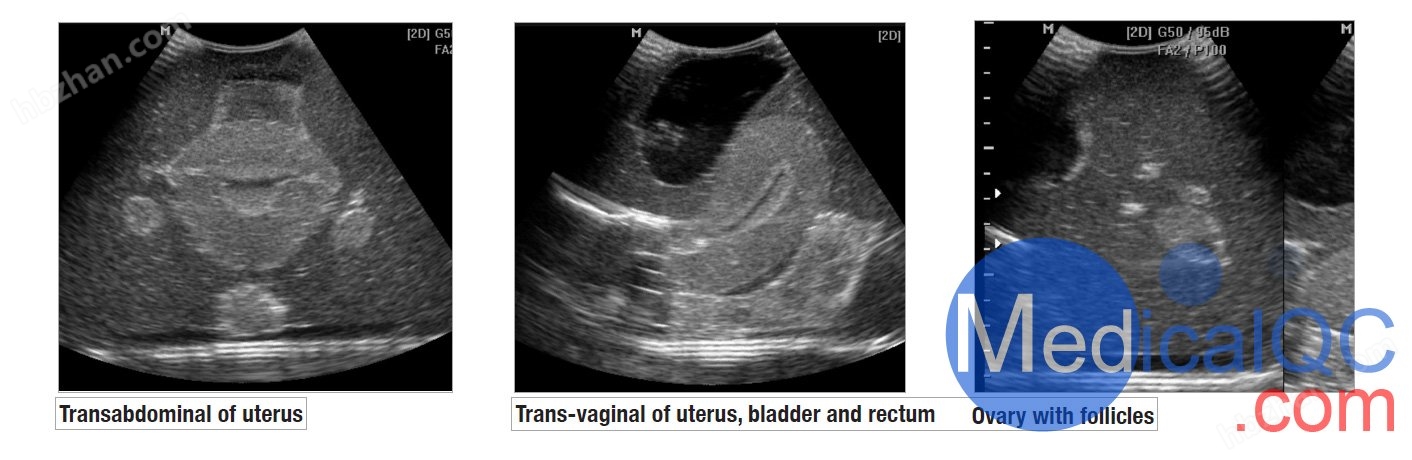

CIrs 404A女性盆腔模体,CIrs 404A超声训练骨盆 模体超声影像图:

CIrs 404A超声训练骨盆模体

我们的CIrs 404A女性盆腔模体,CIrs 404A超声训练骨盆 模体由一个外部女性盆腔模型组成,其中包含用于扫描的子宫、输卵管、卵巢、膀胱和直肠标志。体模具有腹部和阴道扫描通道,允许各种换能器方向。

外部解剖

腹部和阴道扫描通路

子宫内膜和子宫肌层

有卵泡的卵巢

满膀胱

直肠标志物

逼真的扫描